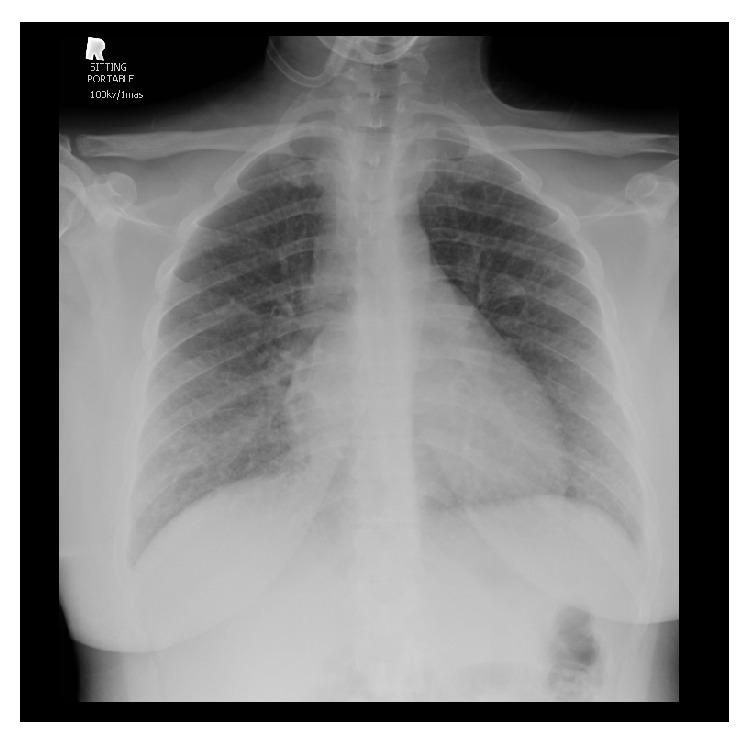

年轻女性不明原发恶性肿瘤的致命性肺肿瘤栓塞性微血管病

Fatal Pulmonary Tumor Embolic Microangiopathy in Young Lady without Known Primary Malignancy.

Pulmonary embolism (PE) is a common cause of morbidity and mortality in hospitalized patients. Malignancy, prolonged recumbence, and chemotherapy are renowned risk factors for development of clinically significant PE. Cancer exerts a multitude of pathophysiological processes, for example, hypercoagulability and abnormal vessels with sluggish circulation that can lead to PE. One of the peculiar characteristics of tumor cells is their ability to reach the circulation and behave as blood clot-not a metastasis-occluding the pulmonary circulation. We present a case of fatal pulmonary embolism diagnosed histologically to be due to tumor cell embolism.

摘要

肺栓塞(PE)是住院患者发病和死亡的常见原因。恶性肿瘤、长期卧床和化疗是临床上显著PE发生的著名危险因素。癌症会引发多种病理生理过程,例如高凝状态和血管异常伴循环缓慢,进而可能导致PE。肿瘤细胞的一个独特特征是它们能够进入循环系统并表现为血凝块——而非转移灶——阻塞肺循环。我们报告一例经组织学诊断为肿瘤细胞栓塞导致的致命性肺栓塞病例。